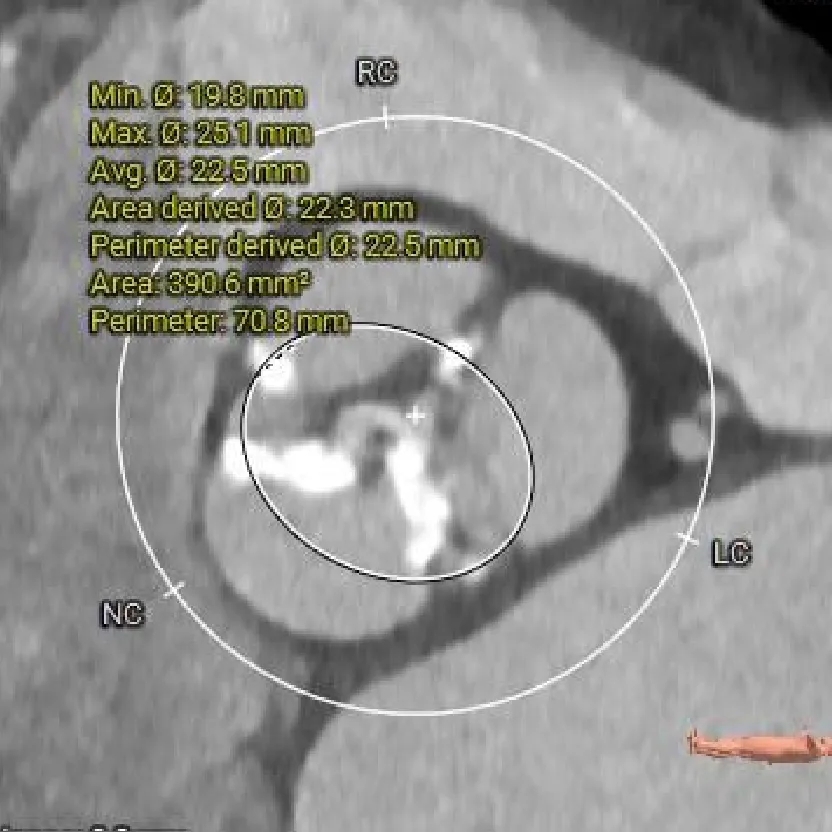

主动脉根部测量

Annulus

25mm

LVOT

钙化积分

601mm3

SOV:

28*27.8*26.8mm

STJ:

26.4mm

瓣上结构测量

瓣上2mm

瓣上4mm

25.3mm

瓣上6mm

24.2mm

瓣上8mm

24.8mm